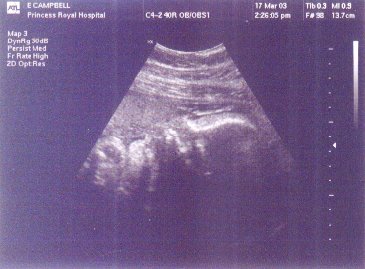

I have now put my newer scan pics, from the 17th of March, up here as you can see to the left. Because they were done at 32 weeks the baby is really big now and all you can fit into the scan is its head and hand. It looks like it could be sucking its thumb.